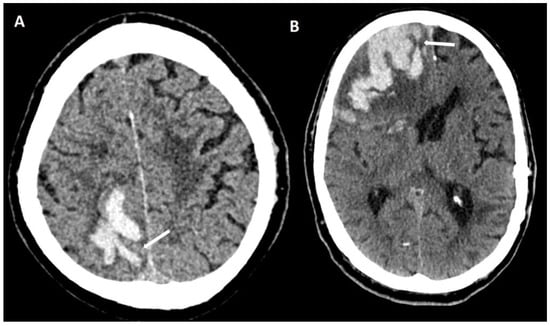

5.1.1. Lobar Hemorrhages

- Baron, J.-C.; Boulouis, G.; Benzakoun, J.; Schwall, C.; Oppenheim, C.; Turc, G.; Varlet, P. Cerebral amyloid angiopathy-related acute lobar intra-cerebral hemorrhage: Diagnostic value of plain CT. J. Neurol. 2022, 269, 2126–2132. [Google Scholar] [CrossRef]